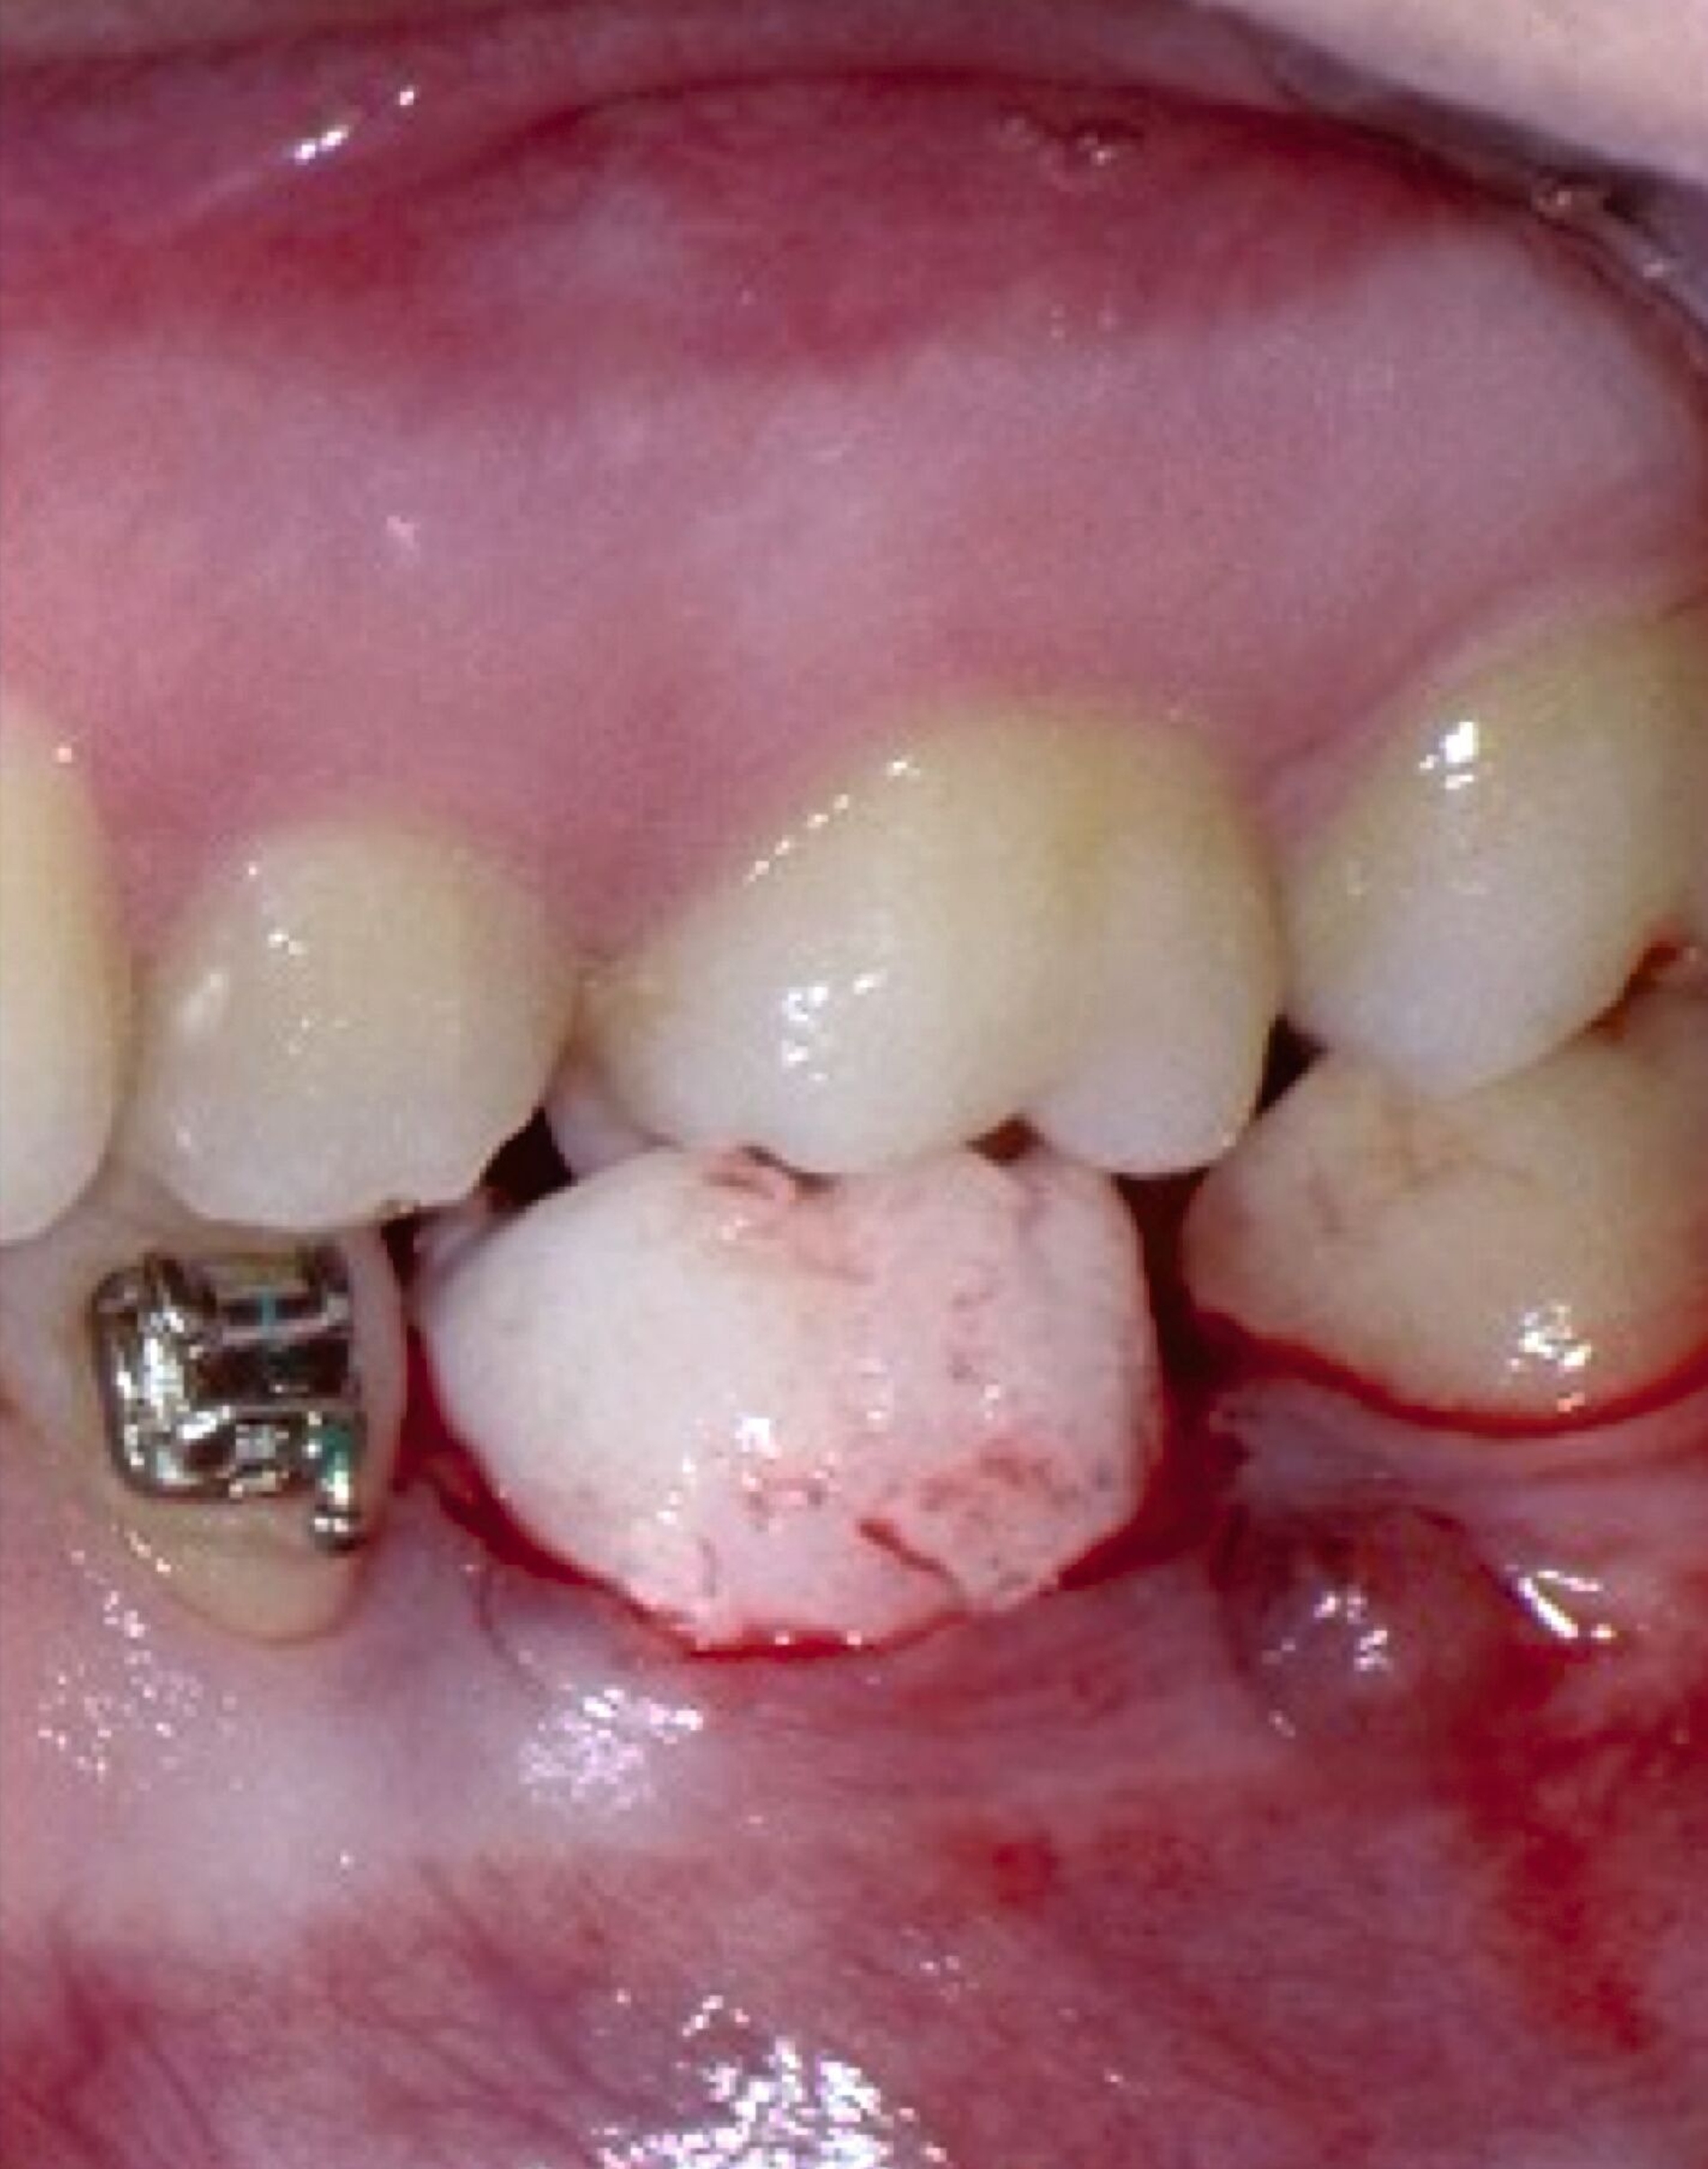

Weitere Beispiele beinhalten hochkomplexe Behandlungsfälle multipler Zahnanlagen. Während die Extraktionsentscheidung und Absprache mit dem/der chirurgisch tätigen Kollegen/in allein auf Basis der Bildgebung oft limitiert ist, erleichtern 3-D-gedruckte Modelle des segmentierten DVTs sowohl die Entscheidung als auch die Absprache und ermöglichen darüber hinaus eine genauere Planung des chirurgischen Vorgehens (Abbildung 6c). Gleiches betrifft parodontalchirurgische Eingriffe, in denen sogenannte „Cutting guides“ eine zuvor digital geplante Gingivektomie ermöglichen (Abbildung 6d). Im Bereich der Freilegung verlagerter Zähne können Schablonen dem/die chirurgisch tätigen Kollegen/in sowohl die Freilegung des Zahnes (Abbildung 6e) als auch die Anbringung eines Attachments (Abbildung 6f) erleichtern und dabei die kieferorthopädisch gewünschte Attachmentposition passgenau übertragen.